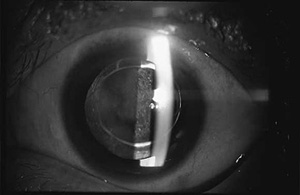

図2 白内障の目

図3 水晶体嚢の中の濁った水晶体を超音波で吸い出します。

図4 取り除いた水晶体のかわりに眼内レンズを挿入します。

眼内レンズは、光学部と支持部から成り(図5)、残された薄い膜(水晶体嚢)の中に、このレンズが固定されます。大きさは全体が12~13mmで、非常に小さな形をしており、コンタクトレンズをさらに小型にしたような形をしています。

図5

図6 水晶体嚢が濁った後発白内障の目

図7 濁った水晶体嚢にレーザー光線で穴をあけて再びよい視力を取り戻します。